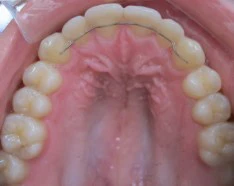

Encombrement dentaire chez un adolescent

L’encombrement dentaire chez cet adolescent a été corrigé grâce à un appareil dentaire de bagues métalliques. La stabilisation pour éviter la récidive est faite grâce à un fil de contention orthodontique comme vu sur la photo et grâce à une gouttière dentaire de contention à porter toutes les nuits pendant une année.